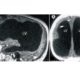

В публикации говорится о так называемом «мозговом тумане», представляющим собой долговременное последствие перенесённого заражения коронавирусом. Пациенты, переболевшие коронавирусом озвучивали жалобы на наличии у них апатии, повышенной утомляемости, депрессии, проблем со сном, ухудшение памяти и снижение концентрации внимания.

Специалистами было установлено, что «мозговой туман» в течение одного года способен отнять у человека до шести баллов коэффициента интеллекта (IQ). Первоначально наличие дефицита отмечалось в когнитивных областях, имеющих связь с вербальным мышлением, пространственным планированием и памятью.